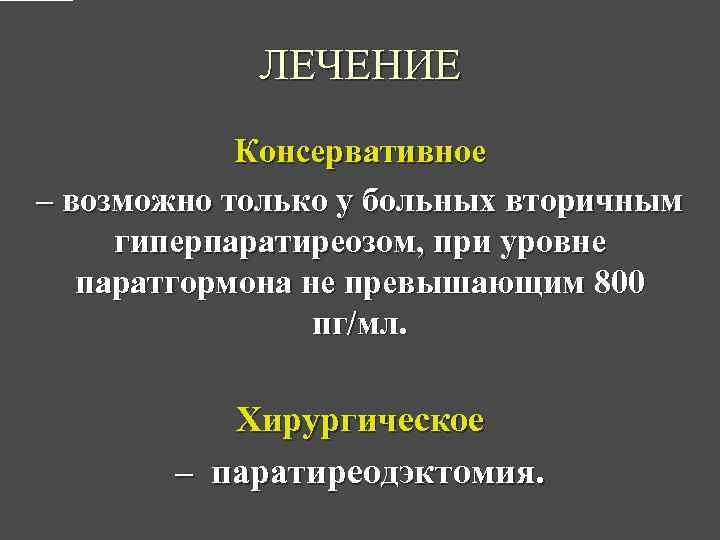

ЛЕЧЕНИЕ Консервативное – возможно только у больных вторичным гиперпаратиреозом, при уровне паратгормона не превышающим 800 пг/мл. Хирургическое – паратиреодэктомия.